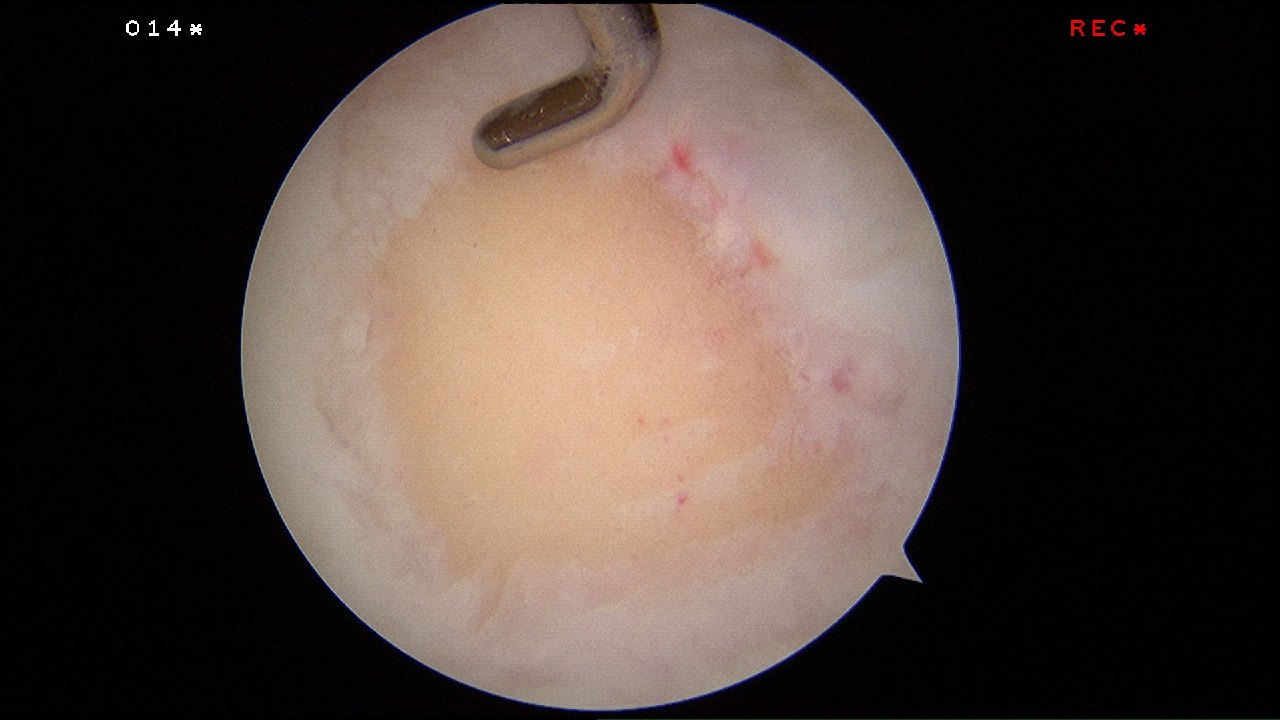

Microfracture surgery is an articular cartilage repair surgical technique that works by creating tiny fractures in the underlying bone.

The tiny microfracture holes cause bleeding from the underlying bone marrow and it forms a so-called super-clot.

The beauty of this surgery is that it is done through key-holes (using arthroscopy) and with easily available tools called chondral picks.

Arthroscopic enhanced microfracture was performed.